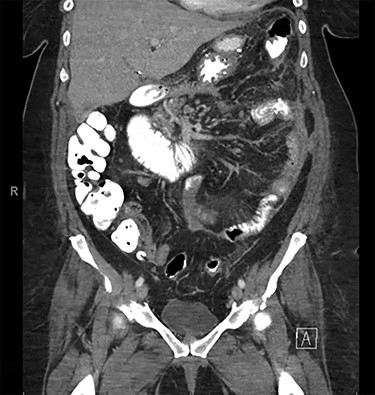

Decision was made to explore and attempt to excise the infarcted omentum. She was taken to the operating room and underwent a diagnostic laparoscopy. However, due to the large size of the omental infarction with an encapsulated necrotic liquefied, purulent secretion and significant adhesions, we decided to convert it to a midline laparotomy. We then proceeded with resection of right-sided infarcted, necrotic, liquefied omentum and abdominal washout (Fig. 3). Culture from the purulent secretion that was inside encapsulated omentum grew Streptococcus anginosus. She received Meropenem and Fluconazole. She had a prolonged and protracted recovery with a transient kidney injury and the development of multiple intra-abdominal (inter-loop, peri-hepatic, peri-splenic and pelvic) fluid collections (Fig. 4A). These collections were treated by percutaneous drainage (pelvis × 1, perisplenic and left-sided collections × 2). Three weeks from the take back, she developed a small bowel obstruction with significant dilation of the biliopancreatic limb and excluded stomach (Fig. 4B and C). She was taken to the operating room and had an endoscopically placed nasogastric tube just passed the jejunojejunostomy. Then, she underwent CT-guided gastrostomy tube to decompress in the gastric remnant (Fig. 5 A and B). One week after the rendezvous nasogastric and gastric remnant decompression, an oral and through the G-tube contrast study demonstrated patency of the gastrojejunostomy and resolution of the small bowel obstruction (Fig. 6). The patient was discharged home on POD #39 tolerating a regular postbariatric surgery diet.

A: Abdominal and pelvic CT scan obtained at POD # 29. From index RYGB and POD # 8 from excision of infarcted omentum showing loculated perisplenic, pelvic and perihepatic fluid collections. B and C: Abdominal and pelvic CT scan obtained at POD # 20 from take back and plain X-ray showing gaseous distention of the excluded stomach and duodenum, confirming a small bowel obstruction of the biliopancreatic limb.